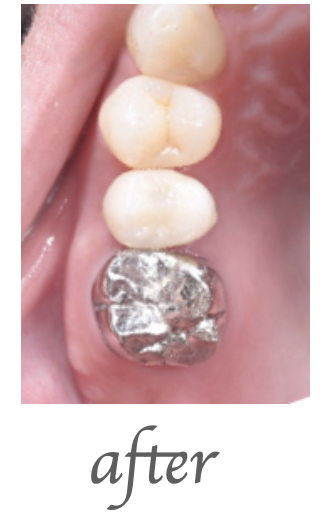

治療内容

右下奥歯の被せの脱離でこられた患者様です。右下の歯の精密根管治療を行いました。

治療期間・回数

治療期間:約2週間 治療回数:3回

費用

¥130,000(税込143,000)

リスク・副作用

処置直後2〜3日は軽微な痛みが出ることがあります。再感染・症状の改善を認めない場合があります。